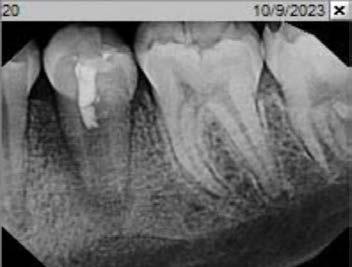

Cover: It’s a tricky situation. Patient with partial denture

Technique for extracting tooth or root tip from underneath fixed partial denture emphasizes use of magnification from dental loupes or dental surgical operating microscope for precision when performing technique-sensitive procedure. Case report.